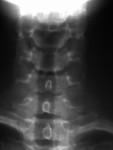

Меня учили смотреть на ункообразные отростки по прямому снимку.

Приложения:

Ну это как бы…

Не обижайтесь, это я показала нормальные УО (ункообразные отростки) у 17 летнего пациента. Они маленькие и кругленькие.

Меня учили, что есть три стадии ункоартроза:

1. УО заострены и удлинены.

2. УО удлинены, заострены и деформированы.

3. УО резко деформированы.

Меня учили смотреть на ункообразные отростки по прямому снимку.

Приложения:

Ну это как бы…

Не обижайтесь, это я показала нормальные УО (ункообразные отростки) у 17 летнего пациента. Они маленькие и кругленькие.

Меня учили, что есть три стадии ункоартроза:

1. УО заострены и удлинены.

2. УО удлинены, заострены и деформированы.

3. УО резко деформированы.